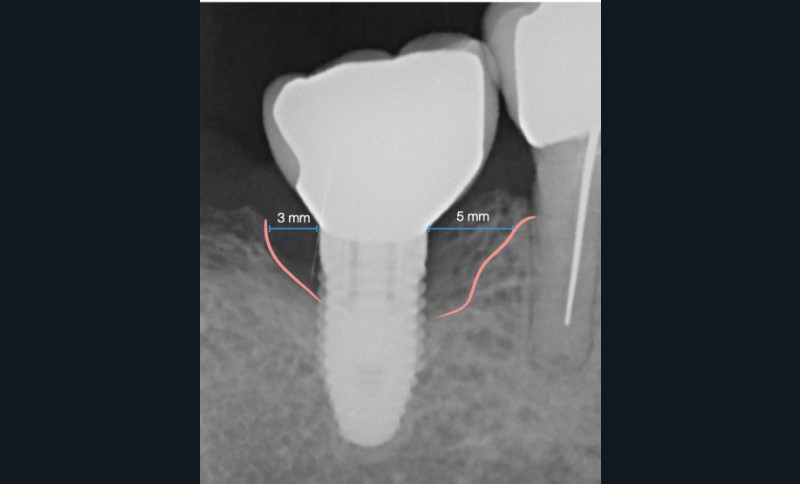

- Péri-implantite sur l’implant 47, diagnostiquée en août 2022

- Poches de 6 à 7 mm

- Implant posé en 2017

- Nobel Replace Select RP (4,1 x 10 mm)